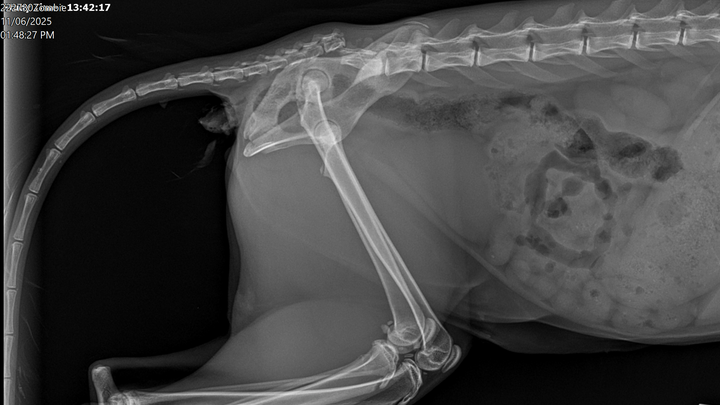

During her visit to Furry Friends, the vet noticed that Zombie reacted strongly when touched near her back end, shifting quickly from calm to distressed. She held her tail awkwardly and walked as though in pain, indicating possible trauma in that area, which had not been mentioned by JPaws. She has never been X-rayed, so these issues had gone undetected before we brought her home.

Since then, Zombie has been to two separate veterinarians. The team at Furry Friends was wonderful and helped stabilize her, but they suspected she might need a tail amputation. They unfortunately lost X-ray capabilities, and Zombie was in too much pain to be examined without sedation, so we took her to Acadiana West Animal Clinic for further evaluation.

Today, November 6th, we received confirmation that Zombie does indeed need a full tail amputation. Despite all she’s endured, she remains the sweetest, most trusting cat, and every vet who’s met her has fallen in love with her gentle spirit.